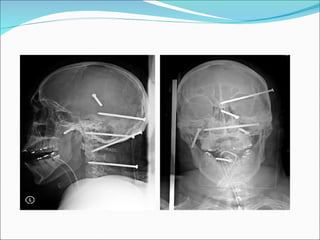

Las lesiones por arma de fuego constituyen una causa mayor de lesión penetrante en Estados Unidos.

LESION PRIMARIA  Estático Existe un agente externo que se aproxima al cráneo con una energía cinética determinada hasta colisionar con él.  Es responsable de fracturas de cráneo y hematomas extradurales y subdurales.  Ocasionan las lesiones focales

HEMATOMA EPIDURAL AGUDO Ruptura arteria  meníngea media. Se suele asociar con fracturas de cráneo, sobre las áreas  que cruzan los surcos de la AMM  75% de los hematomas epidurales ocurren en la región escamosa del hueso temporal .